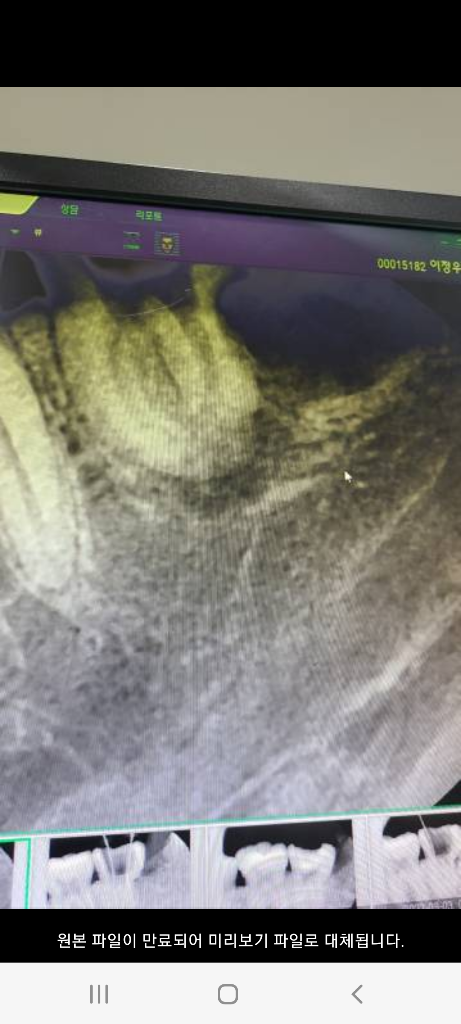

1. 1번째 사진 - 22.08 처음 치과간날 사진

(사랑니 발치 전)

• 1번 째 사진